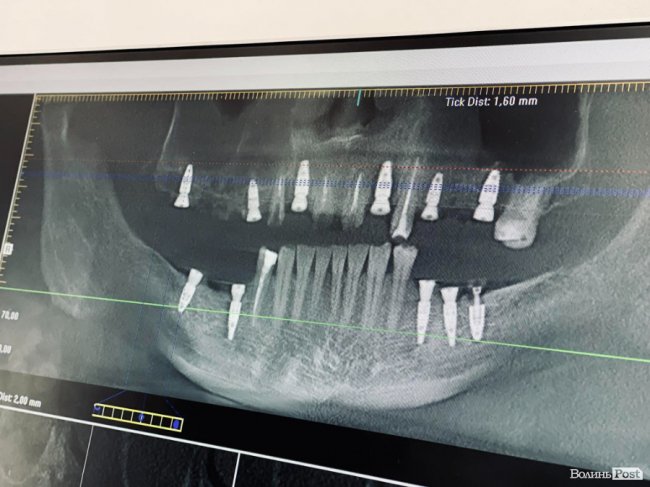

Також перед візитом до лікаря варто зробити комп’ютерну томографію, щоб спеціаліст чітко розумів,яка кількість імплантатів необхідна, чи потрібно видаляти зуби, та чи треба підсаджувати кістковий матеріал. Далі зі своїм знімком ви приходите на консультацію до хірурга-імплантолога і вже тоді отримуєте відповіді на всі свої запитання.